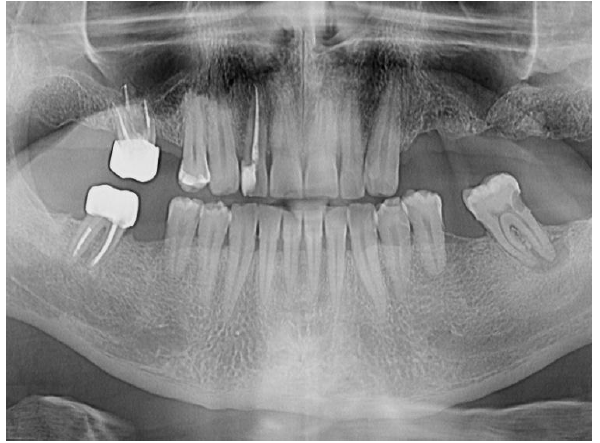

A 52-year-old male patient presented in 2021 with acute, severe pain localized to tooth 47 (mandibular right second molar). Clinical and radiographic examination revealed a large periapical lesion at tooth 47, despite the presence of a previous root canal treatment, and a compromised tooth 16 with extensive structural loss, subgingival decay, and perforation.

Large periapical lesion on tooth 47

Tooth 16 looks unsavable at this point

OPG shows great healing on 47 at 4 years follow-up